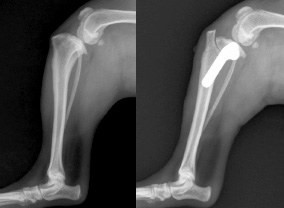

トイプードルやポメラニアン、チワワ、イタリアングレーハウンドなどの小型犬はソファーからの落下などで、前肢を骨折してしまうことが少なくありません。その際、金属製のインプラントを使って整復する必要性があるケースが多いのが現状です。

当院では、従来の治療法に加え、ロッキングプレートを用いた治療も行っております。

ロッキングプレートはプレートにスクリューをロッキングさせて固定するシステムで、手術時間の短縮や合併症の減少が期待できる治療法です。 |